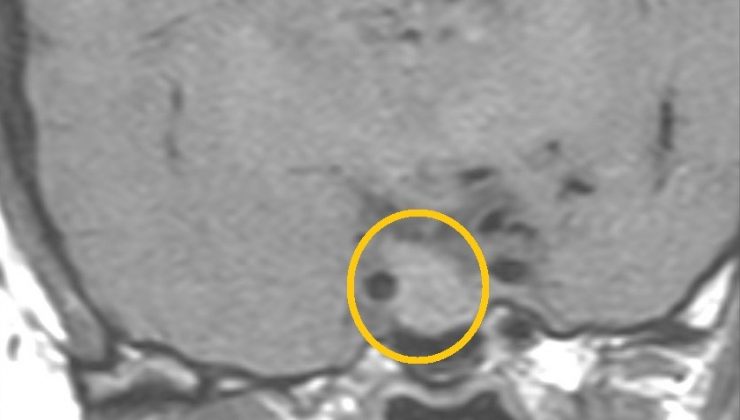

Hipofiz tümörü olan kadın başarılı bir ameliyatla tedavi edildi

Mersin’de baş ağrıları ve adet düzensizlikleri nedeniyle hastaneye başvuran kadında iyi huylu hipofiz tümörü tespit edildi. 41 yaşındaki Hamde Alahmad, kafatası açılmadan burundan girilerek yapılan ve yaklaşık 3 saat süren operasyonla sağlığına kavuştu.

VM Medical Park Mersin Hastanesi’nde adet düzensizlikleri ve baş ağrıları nedeniyle yapılan tetkiklerde hipofiz bezi yerleşimli yaklaşık 2 santimetre boyutlu adenom (iyi huylu hipofiz tümörü) tespit edilen 41 yaşındaki Hamde Alahmad, başarılı bir ameliyat ile tedavi edildi. Kafatası kemiği açılmadan burundan endoskop ve nöronavigasyon gibi yüksek teknolojiler kullanılarak gerçekleştirilen ameliyatı, hastane dışından Kulak Burun Boğaz Uzmanı Prof. Dr. Hayrettin Cengiz Alpay, VM Medical Park Mersin Hastanesi Kulak Burun Boğaz Uzmanı Op. Dr. Aykut Bozan ve Beyin Cerrahisi Uzmanı Prof. Dr. Bora Gürer ile Op. Dr. Ramazan Fesli başarılı bir şekilde gerçekleştirdi.

Çok küçük boyutlarda tesadüfen tespit edilmiş, herhangi bir bulguya ve anormal hormon salgılanmasına neden olmayan adenomların tedavi edilmediğini vurgulayan Prof. Dr. Gürer, “Ancak çeşitli aralıklarla bu adenomların büyüyüp büyümediği takip edilmelidir. Nasıl bir tedavi uygulanacağı adenomun boyutuna, salgıladığı hormonun çeşidine ve neden olduğu bulgulara göre değişir. Bunlara ilaç tedavileri, radyasyon tedavisi ve cerrahi tedaviler uygulanabilmektedir. Bu hastamızda da 3 saat süren başarılı bir cerrahi işlem gerçekleştirilmiş olup, tekrar eski sağlığına kavuşturulmuştur. Tedavi sonrası belirli aralıklarla adenomun takip ve yeniden büyüyüp büyümediği kontrol edilecek” ifadelerini kullandı.